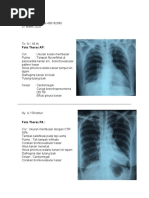

FOTO THORAX AP

PEMBUATAN : BERBARING/SUPINE/TERLENTANG

CIRI : COSTA 1 PIPIH KLAVIKULA LURUS SCAPULA DIDALAM

11/25/17

HEMITHORAX 7